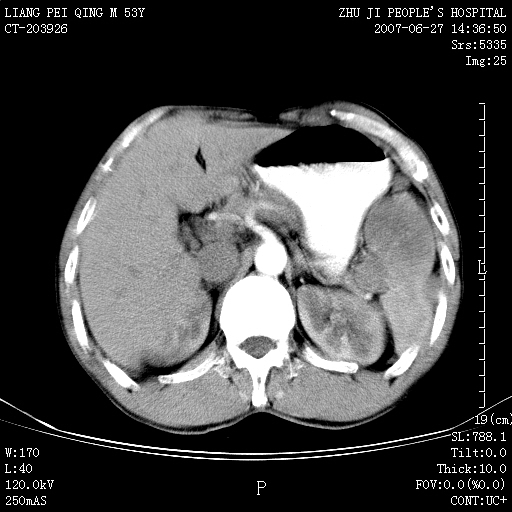

以下是引用余辉在2007-6-27 18:46:00的发言:[br]病灶多发,内可见大片状低密度区,病灶病灶等密度区轻度强化,动脉期后期病灶低密度区与高密度区对度增加,考虑1淋巴瘤2转移瘤3血管内皮细胞瘤(不知有否静脉期及延迟期扫描)

以下是引用zzzzhhhhaaaannnn在2007-6-27 20:44:00的发言:[br]脾脏 肋骨转移可能性大,下腔静脉内有癌栓

以下是引用狙击手在2007-6-28 10:35:00的发言:[br]1:定位:来源于脾脏。2:强化:强化,但不均匀。3:下腔静脉癌栓?下腔静脉充填不均匀与增强时间有关,延时即可明确。4:肋骨破坏?看起来并不确切。综上考虑几个最常见诊断:1;淋巴管瘤;2;血管内皮肉瘤(高度恶性,早期即可转移,常见肝,肺,骨)3;转移瘤(无特征性,只有肝或其它腹腔脏器有类似病变时,才可提示之)